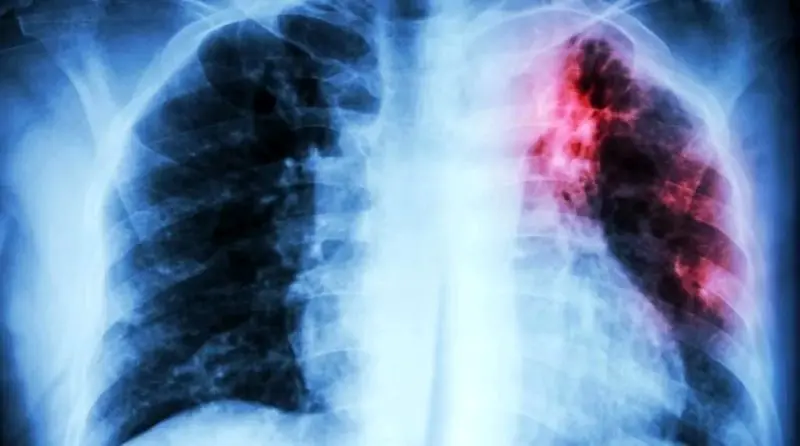

| سازمان بهداشت جهانی (WHO) اعلام کرد که بیماری سل (Tuberculosis) همچنان جایگاه مرگبار خود به عنوان کشنده ترین بیماری عفونی جهان را حفظ کرده و در سال 2024 جان 1.23 میلیون نفر را گرفته است. براساس گزارش جهانی سل 2025، این بیماری عفونی در سال گذشته میلادی کشنده ترین بیماری عفونی بوده است. البته جهان برای اولین بار پس از همه گیری کووید-19، شاهد کاهش هم زمان موارد ابتلا به سل (نزدیک به 2 درصد) و مرگ ومیر ناشی از آن (3 درصد) بوده است. اما WHO هشدار می دهد که این دستاوردها شکننده هستند. مدیرکل WHO دراین باره گفت: کاهش ابتلای جهانی به سل و پیشرفت در آزمایش و درمان، همگی اخبار خوشایندی هستند، اما چنین پیشرفتی به معنای پیروزی نیست. او می گوید اینکه سل به رغم قابل پیشگیری و قابل درمان بودن همچنان سالانه جان بیش از یک میلیون نفر را می گیرد، مسئله بغرنجی است. گزارش سازمان بهداشت جهانی درباره سل بزرگ ترین مانع در مسیر نابودی سل کمبود بودجه است که از سال 2020 راکد مانده است. در سال گذشته میلادی فقط 5.9 میلیارد دلار برای پیشگیری، تشخیص و درمان سل در دسترس بود. این رقم درحالی است که هدف تعیین شده، رسیدن به بودجه سالانه 22 میلیارد دلاری تا سال 2027 است. دکتر ترزا کاسایوا ، مدیر بخش HIV، سل و هپاتیت WHO، هشدار داد: کاهش بودجه و عوامل پایدار اپیدمی، دستاوردهای به دست آمده را تهدید به نابودی می کنند. اما با تعهد سیاسی، سرمایه گذاری پایدار و همبستگی جهانی می توانیم این قاتل باستانی را یک بار برای همیشه ریشه کن کنیم. به گزارش WHO، در سال 2024 حدود 10.7 میلیون نفر به سل مبتلا شدند. بار این بیماری به شدت نابرابر است و 8 کشور 67 درصد کل موارد ابتلای جهانی را به خود اختصاص داده اند: هند (25 درصد) اندونزی (10 درصد) فیلیپین (6.8 درصد) چین (6.5 درصد) پاکستان (6.3 درصد) نیجریه (4.8 درصد) جمهوری دموکراتیک کنگو (3.9 درصد) بنگلادش (3.6 درصد)  پنج عامل خطر اصلی که به این اپیدمی دامن می زنند عبارتند از: سوءتغذیه، آلودگی به HIV، دیابت، سیگارکشیدن و مصرف الکل. سل همچنین قاتل شماره یک افراد مبتلا به HIV است و سال گذشته باعث مرگ 150 هزار نفر در این گروه شد. با وجود چالش های بودجه، پیشرفت در درمان امیدوارکننده بوده است. در سال 2024، 8.3 میلیون نفر جدید مبتلا به سل تشخیص داده شدند و به درمان دسترسی پیدا کردند که یک رکورد تاریخی محسوب می شود و نشان دهنده بهبود سیستم های تشخیص است. همچنین میزان موفقیت درمان از 68 درصد به 71 درصد افزایش یافته است.. با وجود تأثیر مخرب جهانی سل، بیش از یک قرن است که هیچ واکسن جدیدی برای آن مجوز نگرفته و هیچ واکسنی برای بزرگسالان وجود ندارد. اما این وضعیت ممکن است به زودی تغییر کند. درحال حاضر 18 واکسن مختلف درحال آزمایش روی انسان هستند که از این تعداد 6 واکسن در فاز 3 (مرحله نهایی قبل از درخواست تأییدیه) قرار دارند. |